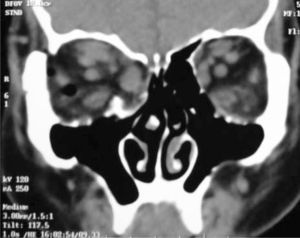

Esta técnica quirúrgica puede asociarse a la extirpación de otra pared orbitaria, el piso logrando un mayor volumen y por ende una disminución de la proptosis. (Figuras 3A y 3B).